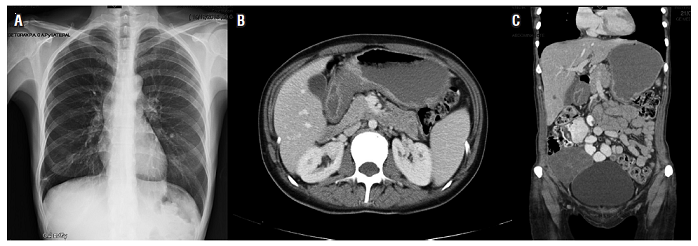

Es valorada por oncología. Se inicia la quimioterapia con capecitabina (1,5 g vía oral, cada 12 horas, del día 1 al 14) y cisplatino (125 mg intravenoso [IV], única dosis) desde el 7 de julio del 2015. Completó 8 ciclos. En sus controles periódicos se detectó un alivio clínico importante, recuperación de su estado funcional y nutricional, mejoría en las cifras de sus marcadores bioquímicos como el ACE, CA 19-9 y del CA-125. El seguimiento mostró desaparición de la ascitis y aumento de la masa ovárica. Por este motivo, se le propuso una nueva laparoscopia, que se realizó el 12 de noviembre del 2015 con el hallazgo de un ICP de 8, sin implantes peritoneales en cúpulas diafragmáticas, estómago móvil sin adherencias y compromiso metastásico del ovario derecho. No hay líquido libre en cavidad abdominal (Figura 2).

Se presentó en junta quirúrgica con la propuesta de cirugía tipo Sugarbaker, dada la respuesta clínica al manejo con la quimioterapia sistémica. La junta concluyó que no hay beneficios con una cirugía citorreductora tipo Sugarbaker por el tipo histológico y el ICP. Se llevó a salpingo-ooforectomía bilateral, procedimiento que se realizó el día 13 de enero del 2016. Los hallazgos fueron tumores sólidos en ambos ovarios, el derecho de 15 cm y el izquierdo de 10 cm, sin adherencias y sin implantes en el peritoneo; las cúpulas diafragmáticas estaban libres, había engrosamiento de las paredes gástricas; y el líquido ascítico fue de 500 mL. La patología mostró ovario y trompa derecha positivos para adenocarcinoma mal diferenciado con componente de células en anillo de sello; invasión linfovascular positiva; y estudio de inmunohistoquímica positivo para queratina 19, queratina 7 y queratina 20. El resultado fue negativo para human epidermal growth factor receptor 2 (HER2), CA-125, Wilms’ tumor1 (WT1), CDX2 y TF1. El ovario izquierdo resultó positivo para compromiso metastásico por adenocarcinoma con invasión linfovascular positiva.

La paciente continuó con quimioterapia, con capecitabina y cisplatino. El día 16 de mayo, por decisión conjunta con la familia, se llevó a cirugía: se realizó la gastrectomía total con disección ganglionar D2. El resultado de patología fue el producto de gastrectomía total, adenocarcinoma gástrico de tipo difuso con células en anillo de sello, lesión de 6 x 5 cm, invasión tumoral hasta la grasa subserosa, invasión linfovascular y neural positivas, bordes proximal y distal libres de tumor, 5 de 17 ganglios positivos para compromiso tumoral, pT3pN2, epiplón negativo para tumor, rotulado diafragma izquierdo negativo para tumor, ganglios de la arteria hepática negativos para tumor, borde esofágico por aparte negativo para tumor y estado de HER2 negativo (Figura 3).